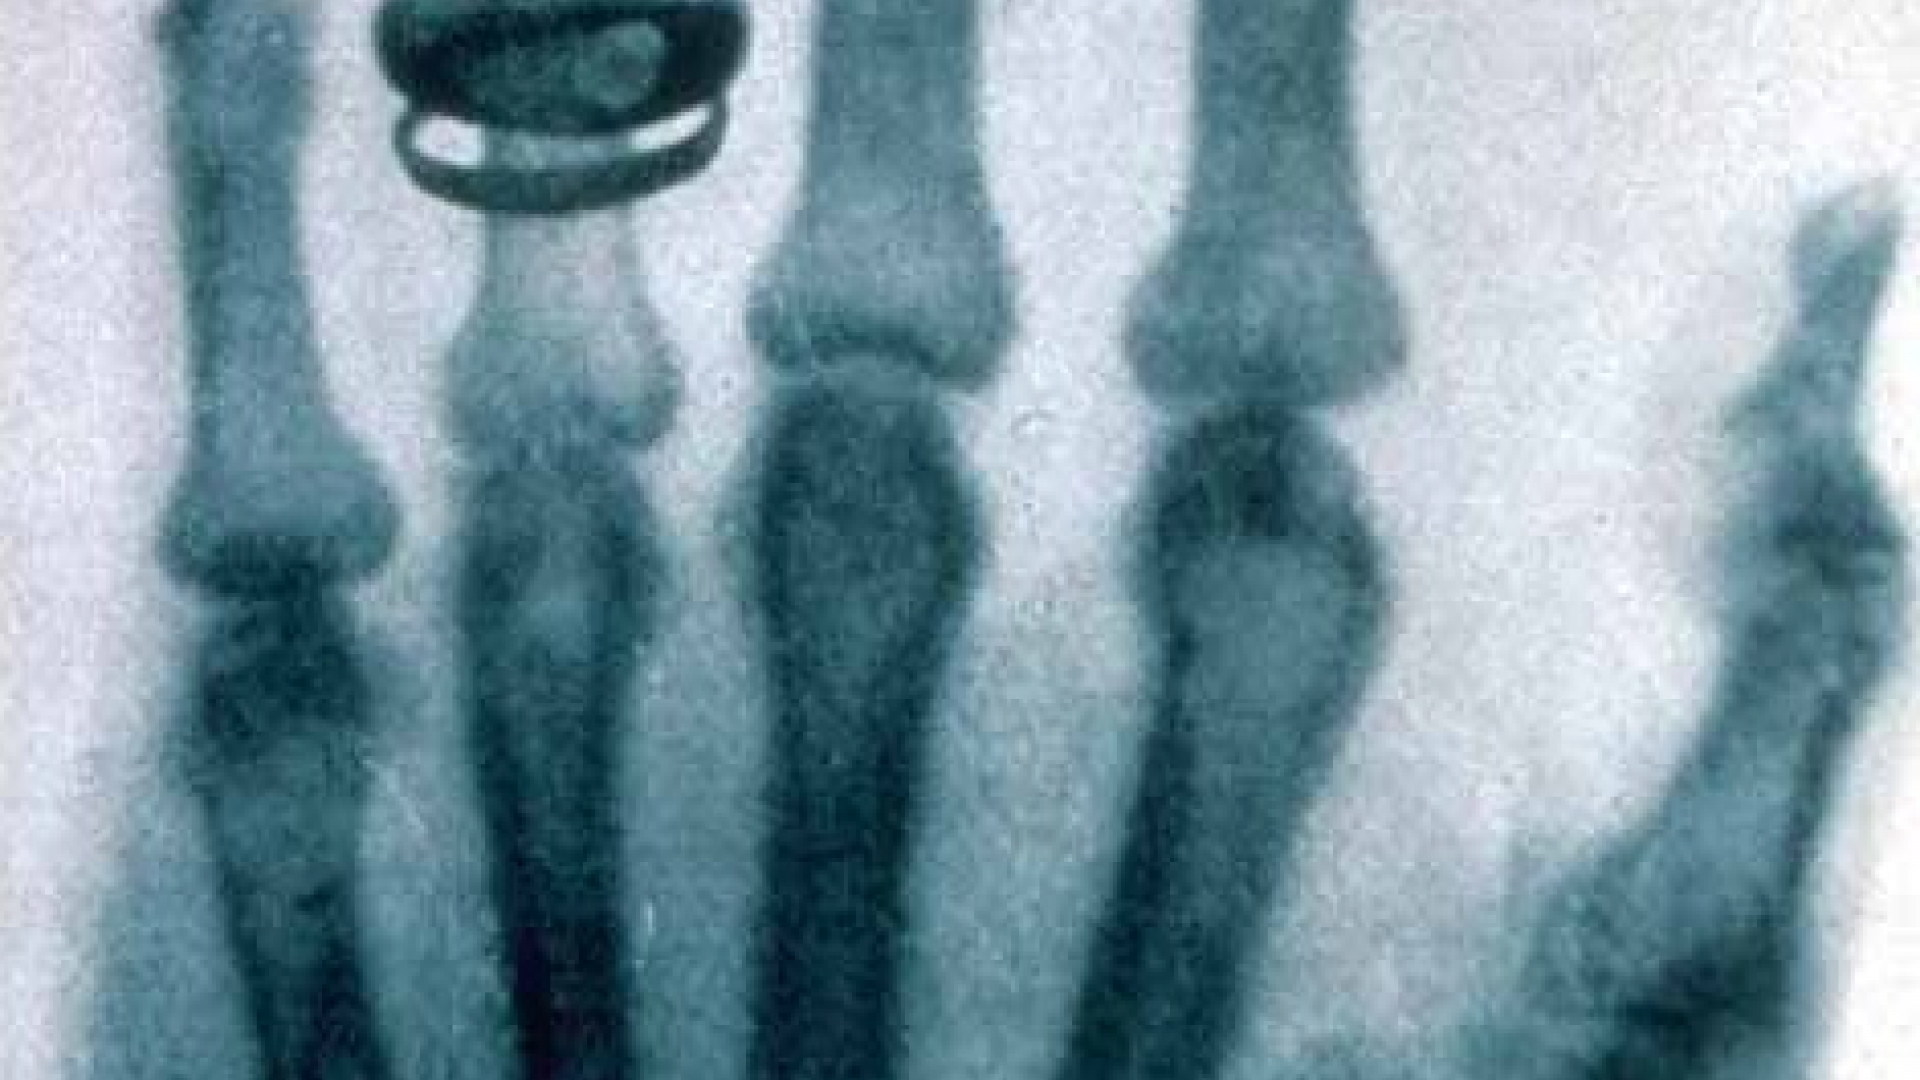

Dieses Röntgenbild einer Hand machte Conrad Röntgen im Jahr 1896.

Und noch etwas entdeckt Röntgen beim Experimentieren: Die Strahlung durchdringt sogar den Körper und hinterlässt auf Fotoplatten Abbilder der Knochenstruktur. Der Forscher teilt seiner Frau daraufhin mit: "Ich mache etwas, wovon die Leute, wenn sie es erfahren, sagen werden: 'Der Röntgen ist wohl verrückt geworden.'" Schon bald macht der Physiker die ersten Röntgenbilder, beispielsweise von der Hand seiner Frau. Wenig später veröffentlicht er seine Entdeckung.